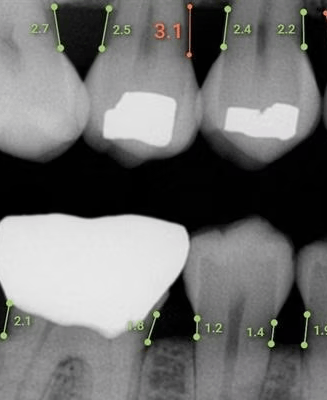

Overjet X-Ray

Overjet is an artificial intelligence (AI) dental software platform that analyzes dental X-rays (radiographs) to automatically detect, outline, and quantify dental conditions such as decay, bone loss, and tartar (calculus) in real time. It creates a color-coded, annotated overlay on top of traditional, black-and-white dental X-rays to help patients and dentists visualize the findings.